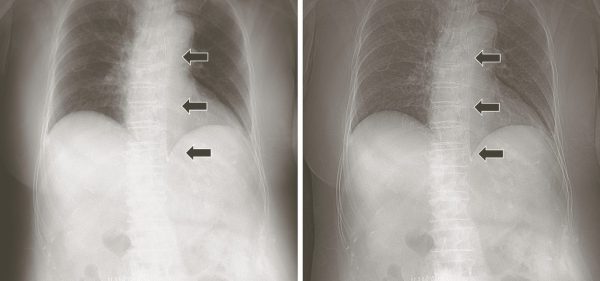

回診撮影では、気管内チューブ、中心静脈カテーテル(CVライン、PICC)、胃管(NGチューブ)、胸腔ドレナージチューブなどカテーテル・チューブ類の留置位置や合併症の確認のために行われることもしばしばある。特に経鼻胃管については、気管への迷入、消化管穿孔などの合併症を考慮し、2018年9月に医療事故調査・支援センターより「胃管挿入時の位置確認はX線画像やpH測定を含めた複数の方法で確認することが望ましい」、「ただし、X線撮影を行なったとしても、正確に胃穿孔を示唆する誤挿入を診断できなかった例もある」と提言された1)。そのため、複数名での確認を行い、カテーテル類挿入後の撮影はただ単に先端位置の確認だけではなく、その走行に異常がないか確認しなければない2)。

そのためには、カテーテル類の走行から先端までを確認しやすい画像が必要になるが、カテーテル類の不透過性の程度や位置、椎体や骨との重なり具合等により、視認しづらい場合がある。その場合は事前にプリセットされた周波数処理条件を選択することで、視認が可能になる(図3)。

a 周波数変更前

b 周波数変更後